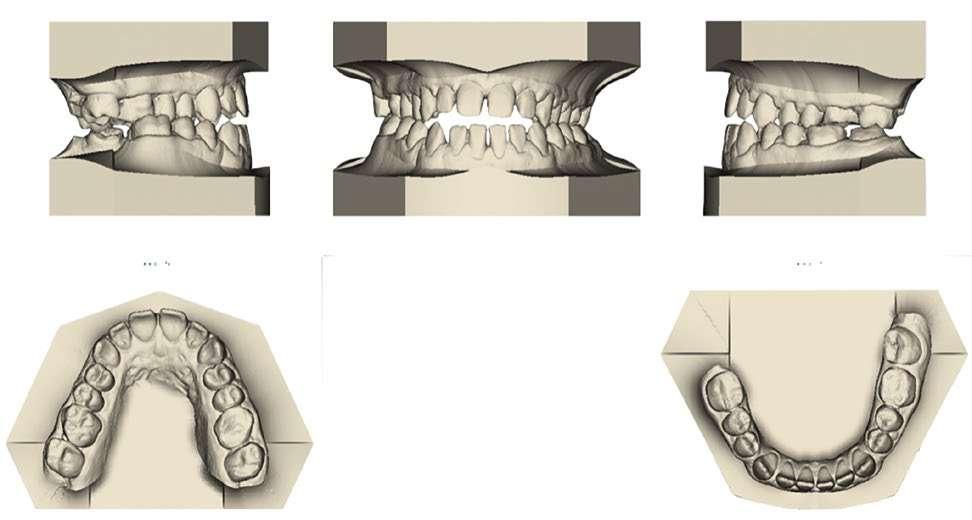

Ilustración 3. Modelos iniciales de estudio.

Ilustración 6. Superposición del modelo inicial (azul) modelo y post-disyunción (gris).

Initial

Post-disjuncion